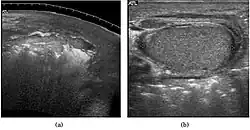

Seminoma is the most common tumor type in cryptorchid testes. The risk of developing a seminoma is increased in patients with cryptorchidism, even after orchiopexy. There is an increased incidence of malignancy developing in the contralateral testis too, hence sonography is sometimes used to screen for an occult tumor in the remaining testis. On US images, seminomas are generally uniformly hypoechoic, larger tumors may be more heterogeneous [Fig. 3]. Seminomas are usually confined by the tunica albuginea and rarely extend to peritesticular structures. Lymphatic spread to retroperitoneal lymph nodes and hematogenous metastases to lung, brain, or both are evident in about 25% of patients at the time of presentation.